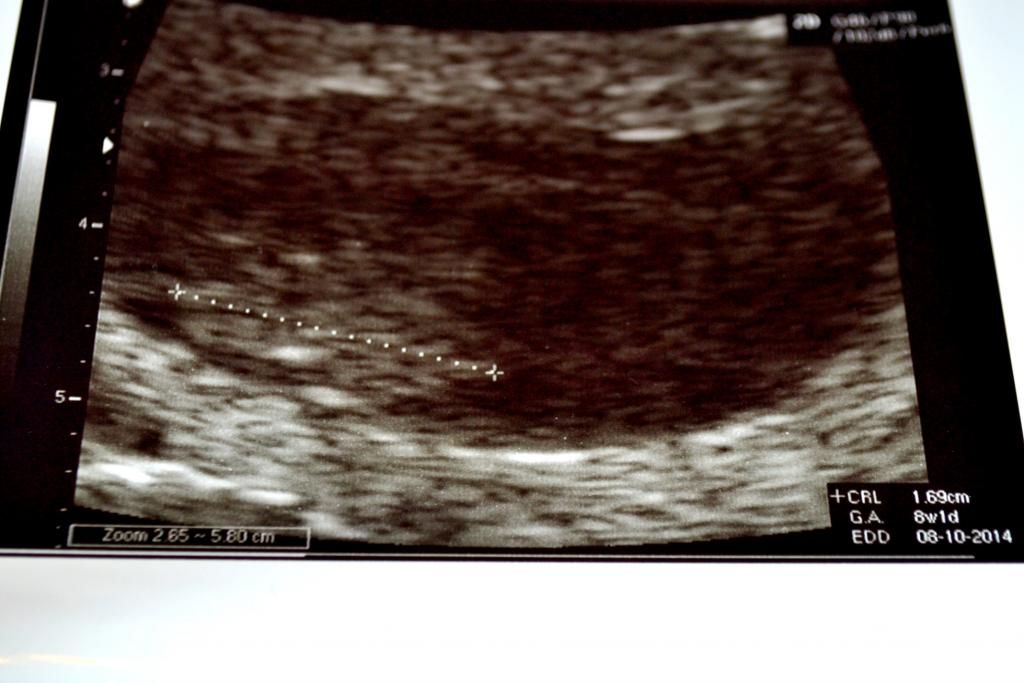

konden gelijk doorlopen. we vroegen kan het nu ook uitwendig, want van dat inwendige gedoe! had ze nu ook wel genoeg van, ja hoor geen probleem, hop gel erop en kijken maar. ff goed kijken inzoomen en JA hoor daar was je. je hartje klopt nog steeds super goed, en je bent 0,45cm gegroeit, je crl komt uit op 8 w 2 d, ietsje korter als 18-02-14 maar dat kon zijn door de uitwendige echo, inwendig was je ook beter te zien , en waarschijnlijk wat groter, maar dit was voor ons niet nodig je hartje klopt en je groeit, je was zelf iets aant bewegen zo schattig, ja viel kan je niet zien op de echo, maar voor ons genoeg,

27/02/14 crl 1,69cm